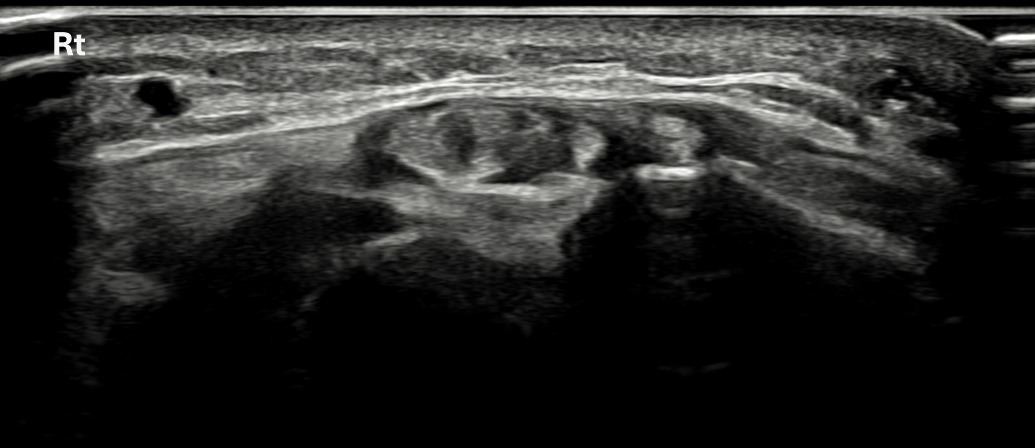

치료 후기에 사용된 전/후 검사 사진은 동일 인물의 결과이며 각 지점 동일 조건에서 촬영되었습니다.

개인에 따라 치료 결과에 차이가 있을 수 있으며, 부작용이 발생할 수 있습니다. 내원 후 충분한 상담을 받으시고 치료를 진행하시면 됩니다.

- 치료기간 : 25 .5 30 . ~ 25 . 6 .27

- 치료횟수 : 5 회(dna 1cycle)